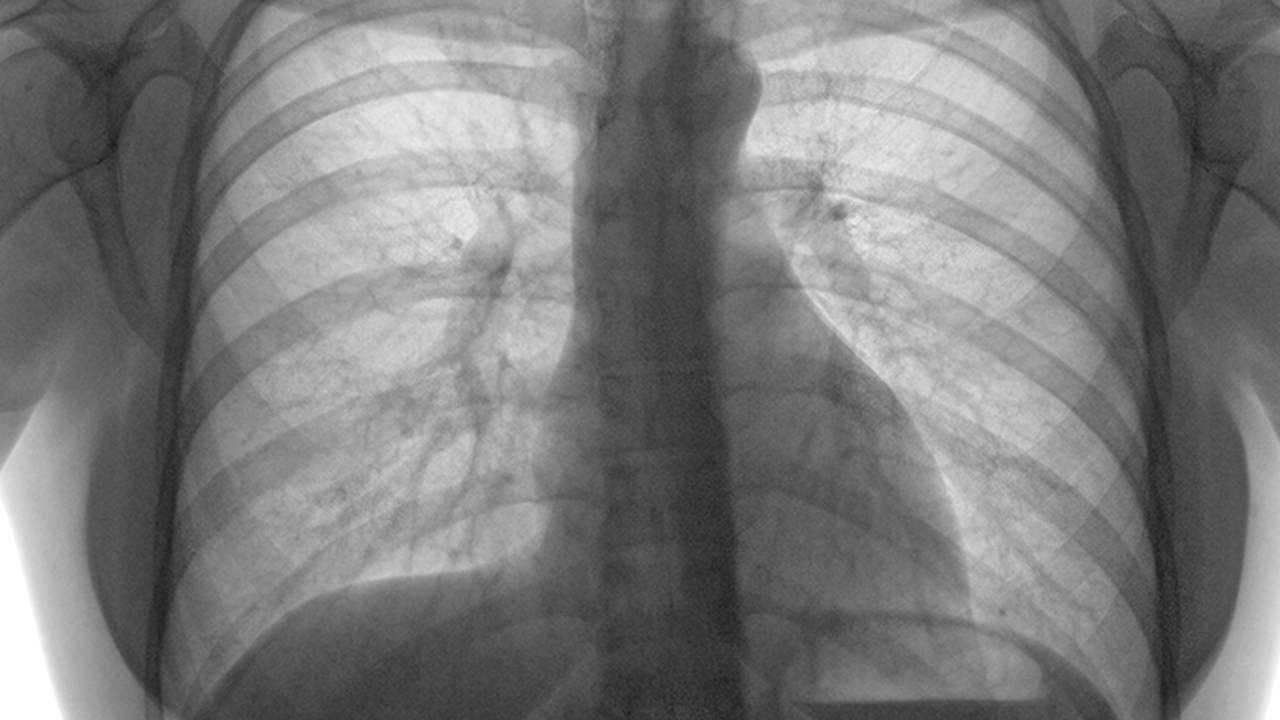

肺癌的发病原因复杂,包括吸烟、空气污染、职业暴露、遗传因素等。早期发现和治疗对提高生存率至关重要,因此选择一家专业的医院进行诊治尤为重要。

肺癌预防与健康管理方面,建议40岁以上人群,特别是长期吸烟者、有肺癌家族史者、长期接触致癌物质者,应定期进行低剂量螺旋CT筛查。戒烟是预防肺癌有效的措施,同时应避免二手烟暴露。保持健康的生活方式,包括均衡饮食、适量运动、保持良好心态,都有助于降低肺癌风险。对于已经确诊的患者,应积极配合治疗,定期复查,保持良好的生活习惯,提高治果和生活质量。